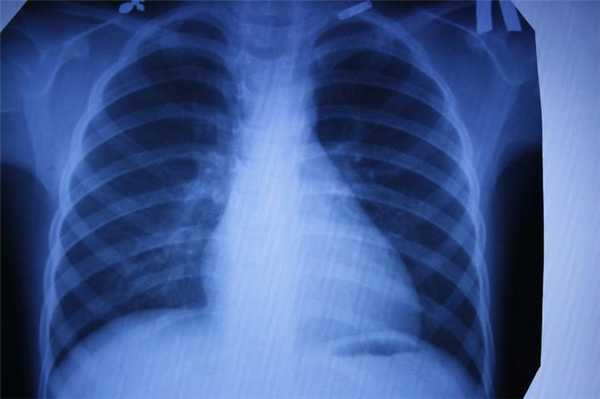

- воспаление легких;

- рак молочной железы;

- туберкулез.

Рентген

Наиболее старый и привычный метод визуализации человеческого тела. Применяют рентген повсеместно, от хирургии до стоматологии. Метод прост и понятен: человека облучают особыми лучами, которые легко проходят сквозь мягкие ткани и задерживаются в твёрдых. Благодаря этому принципу, на фотоплёнку или датчик, расположенные на противоположной от источника лучей стороне, передаётся изображение, а в распоряжение врача попадает рентгенография или рентгеноскопия.

Главные плюсы такого обследования: быстрота и стоимость. Рентгеновскими аппаратами оснащены практически все больницы, процедура проходит быстро и стоит недорого.

Главные минусы: облучение и качество изображения. При проведении рентгенографии пациент облучается, а картинка получается двумерной. Врач с трудом может разглядеть внутренние органы по отдельности, поскольку их тени перекрывают друг друга. Также невозможно детально разглядеть хрящевую ткань и мозг. Хрящи практически не задерживает лучи, мозг надёжно закрыт черепной коробкой. Для их исследования рентгенография не подойдёт.

Наиболее эффективно будет проводить рентгенографию при повреждениях костей, суставов и зубов.

Рентгенография

Принцип работы рентгеновского аппарата заключается в том, что рентгеновские лучи, проходя через разноплотную среду исследуемой области, по-разному ослабляются: более плотная костная ткань в значительной степени поглощает рентгеновское излучение, менее плотная подкожно-жировая клетчатка ослабляет его в небольшой степени, а воздух, содержащийся в околоносовых пазухах или легких, не задерживает совсем. Эти неравномерно ослабленные пучки рентгеновских лучей, попадая на светочувствительный слой пленки, формируют рентгенограмму — изображение, которое отображает все структуры исследуемой области, наслаивая их друг на друга. При этом получаемый снимок позволяет определить форму, размеры и строение исследуемой области, выявить или заподозрить структурные нарушения, а исследование в двух или нескольких проекциях позволяет определить локализацию выявленных изменений. Чаще всего рентгенография используется для исследования костей, легких, почек, кишечника.

C самого начала существования этот метод диагностики вызывал у пациентов множество вопросов по поводу воздействия рентгеновского излучения на организм. На сегодняшний день специалисты подтвердили вред рентгена и его способность влиять на развитие нежелательных процессов в организме. Тем не менее, этот метод лучевой диагностики продолжает пользоваться спросом, поскольку требует минимальных затрат.